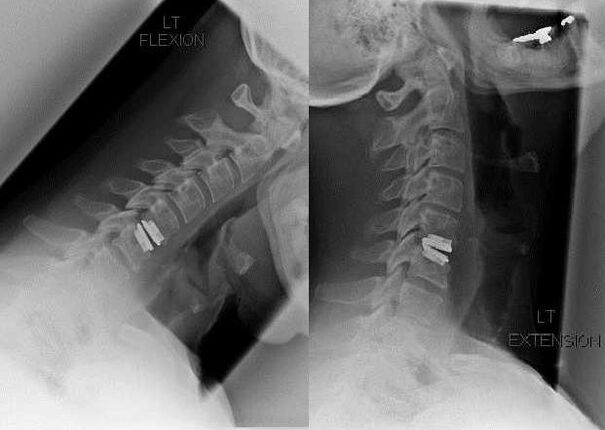

Surgical intervention

Indications for surgical intervention include the ineffectiveness of conservative treatment, as well as complications of cervical osteochondrosis, for example, discogenic myelopathy, vertebral artery syndrome and radicular syndrome.To decompress the spinal cord, blood vessels and spinal roots, the following operations are performed:

During the operation, bone fragments and ligaments may be cut out, and intervertebral discs may be removed in whole or in part.For small hernial protrusions, laser vaporization of the disc core is often performed.

After excision of vertebral structures, stabilization of spinal motion segments is often required by spinal fusion or installation of bone and dermal autografts.